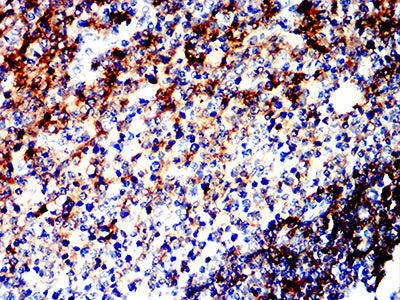

分类: 科研抗体货号: 32329别名: LCA; LY5; B220; CD45; L-CA; T200; CD45R; GP180应用: IHC,FCM反应种属: Human